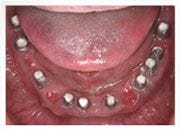

植入植體